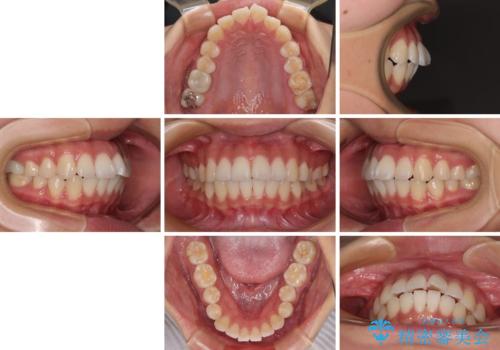

- 前歯が突出して、眠るときに口が開いてしまうことを気にして来院された患者様です。

横から見た際の口元の飛び出した印象も改善したいとのことで、上下左右の第一小臼歯4本を抜歯し、ワイヤー装置にて抜歯矯正を行うこととしました。

舌の突出癖改善のためのトレーニングをしっかりと実践してくださり、2年強の治療期間でしっかりと仕上げることができました。